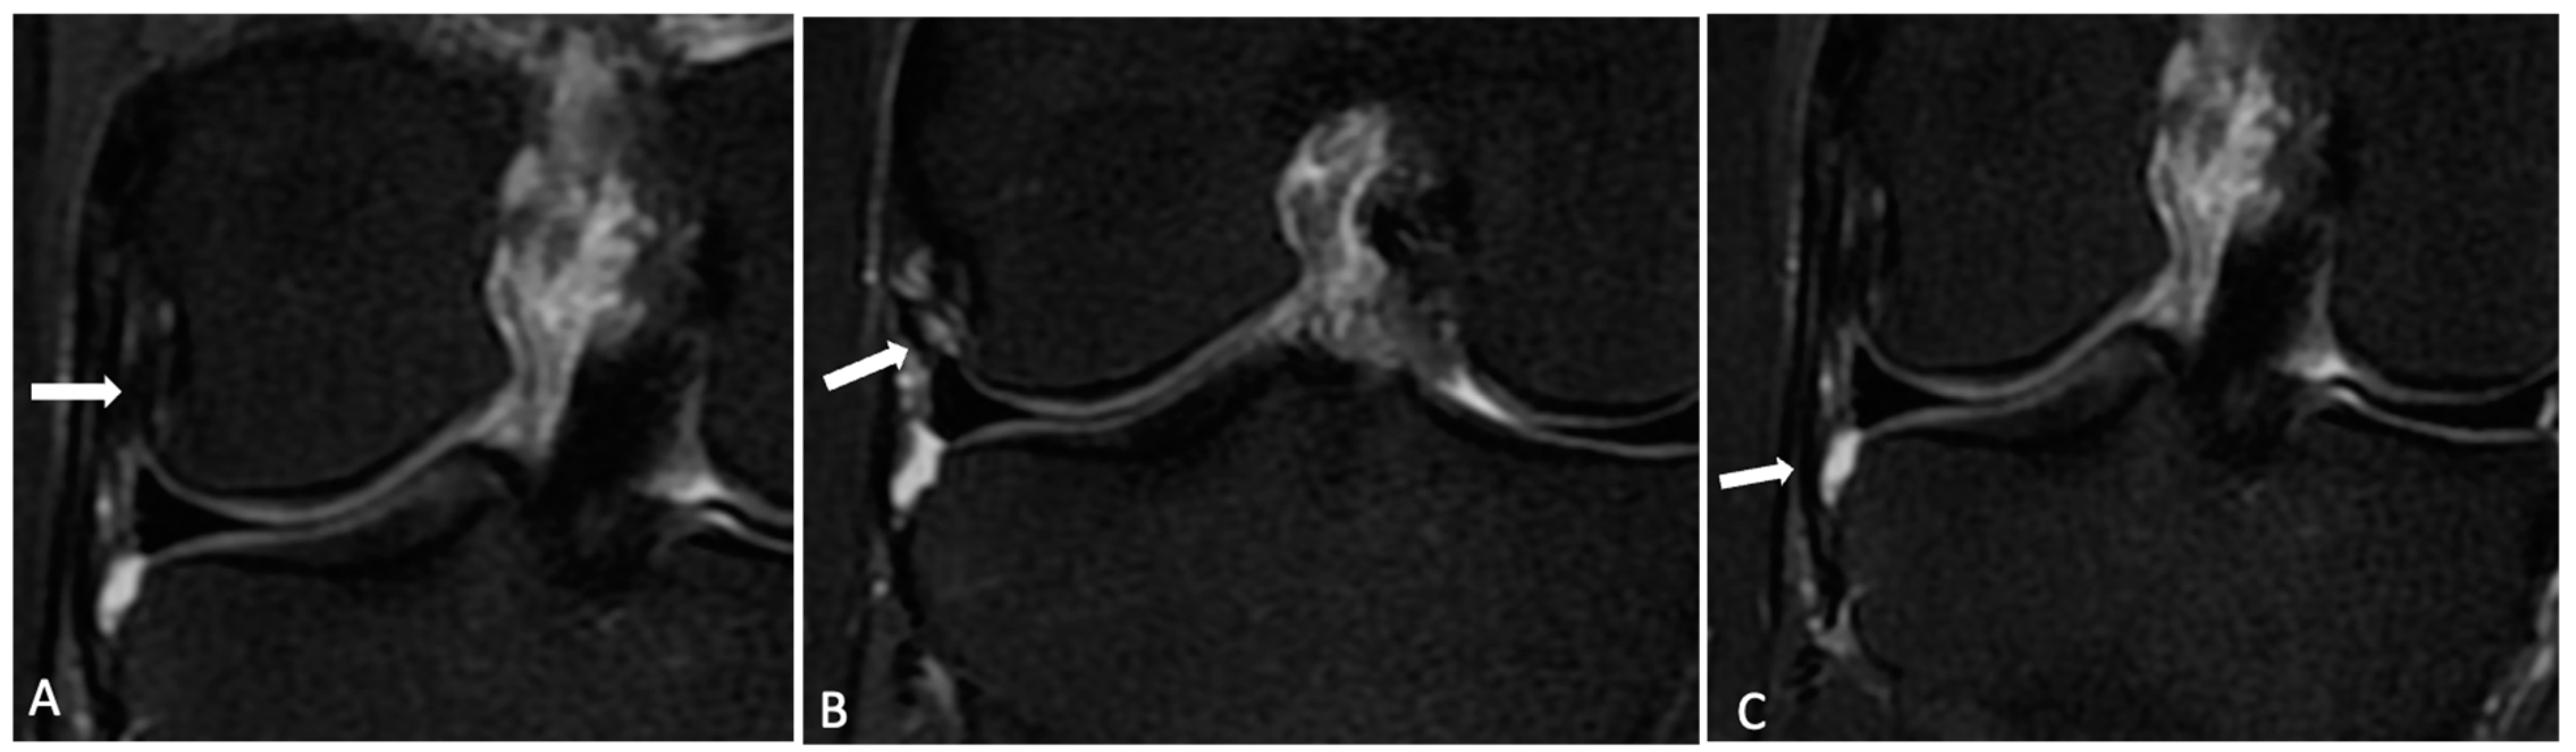

2.2. Radiological Analysis